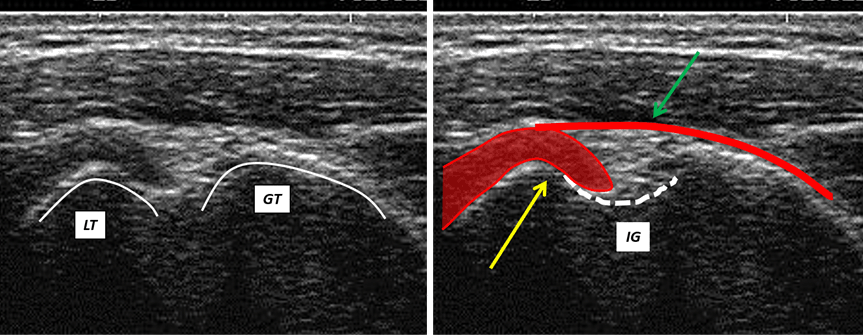

The ultrasound transversal view can be classified into four types (Figures 1,2,3,4).

Figure 3: Ultrasound transversal view Type III: The fibers (yellow arrow) of the SCM tendon insert into the IG of the humerus and, by means of aponeurotic fibers (green arrow), extend above the LHBM tendon as far as the greater tubercle; LT = lesser tubercle; GT = greater tubercle; IG = intertubercular groove.